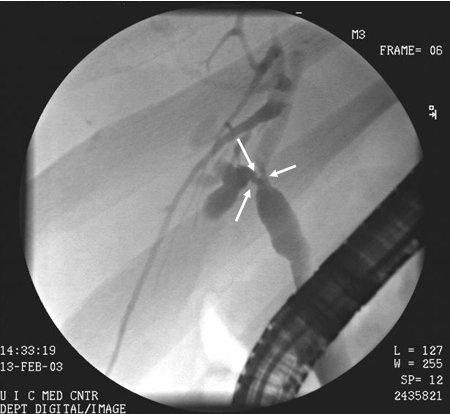

Cholangiocarcinoma

ERCP image of hilar cholangiocarcinoma: Klatskin's tumour with stricture of duct bifurcation (arrows)

From the collection of Dr Joseph Espat; used with permission